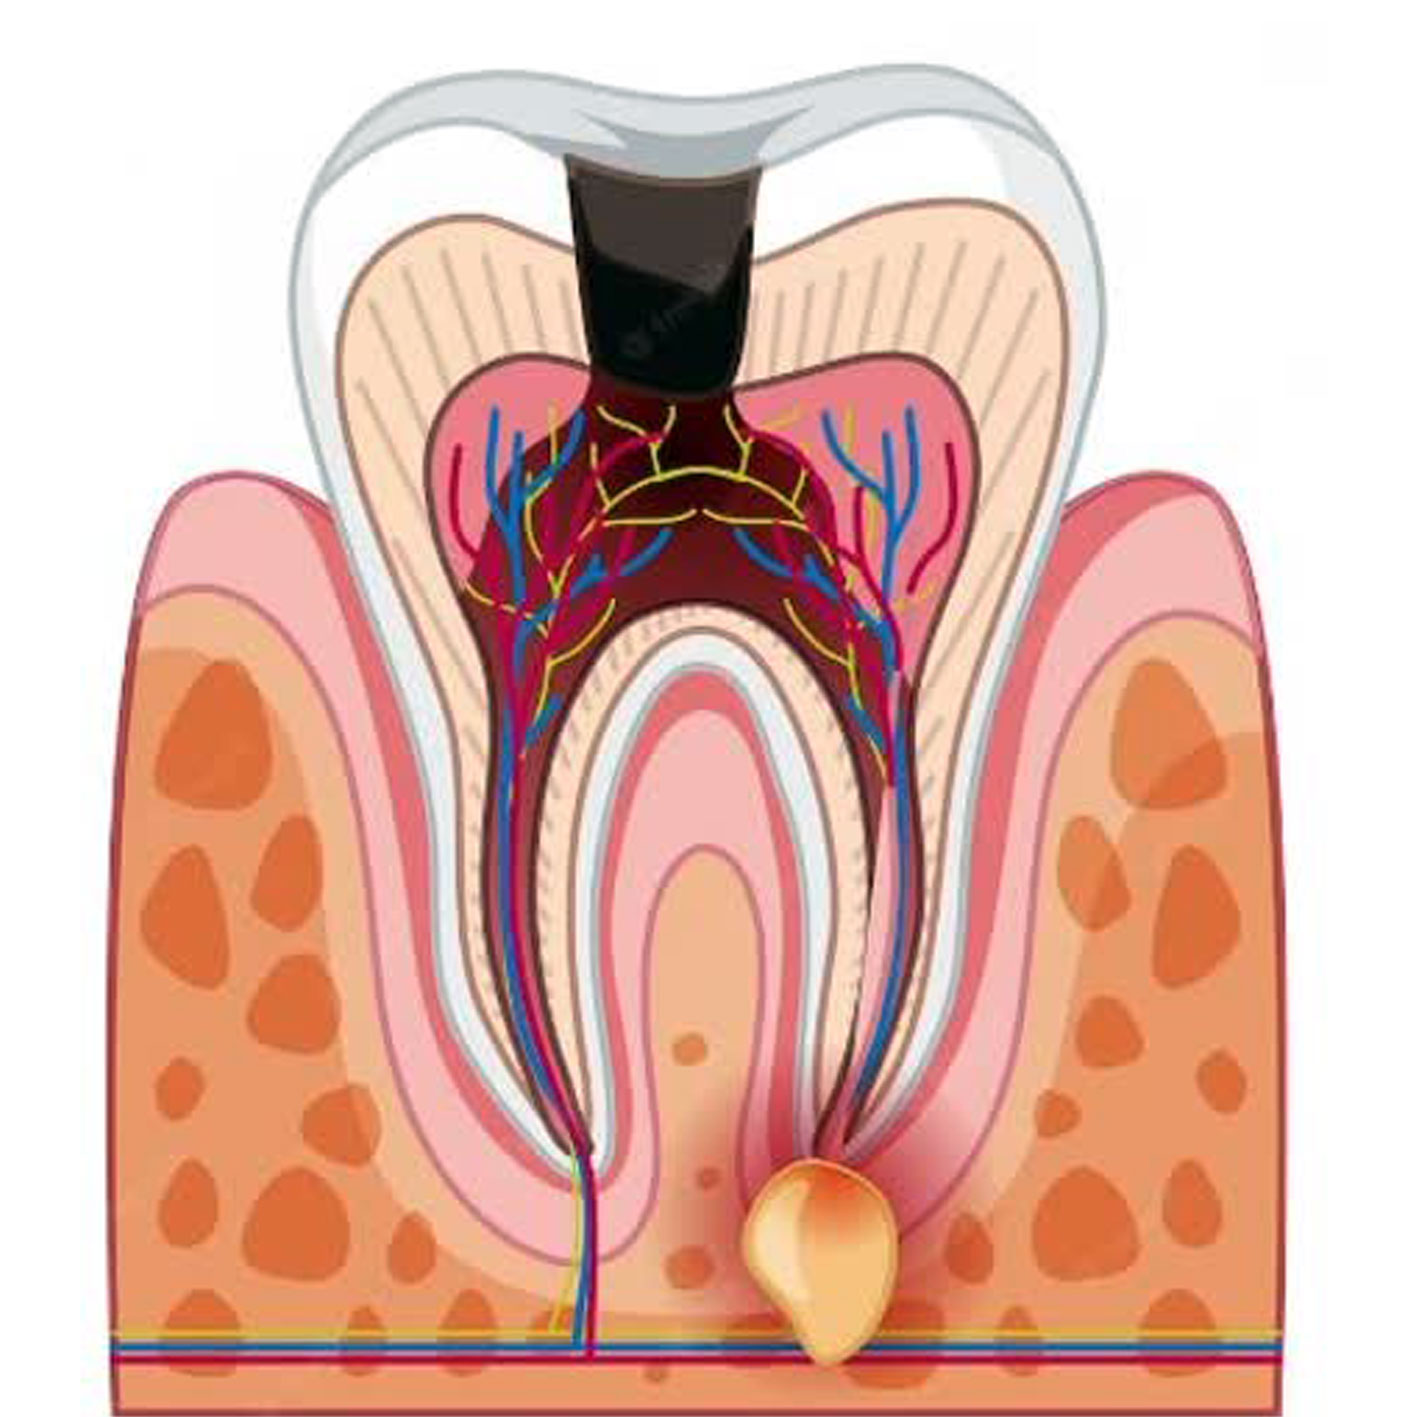

عصب کشی در مواردی انجام می شود که پالپ آسیب برگشت ناپذیر دیده باشد و چاره ای به جز تخلیه و تمیز کردن آن و پر کردن آن با مواد پر کننده مخصوص، وجود نداشته باشد . علت آسیب دیدن پالپ معمولا یکی از موارد زیر است:

پوسیدگی عمیق دندان که درمان نشده و به پالپ رسیده است.

نشت پرکردگی قدیمی یا نامناسب که باعث شده زیر آن پوسیدگی اتفاق داشته باشد .